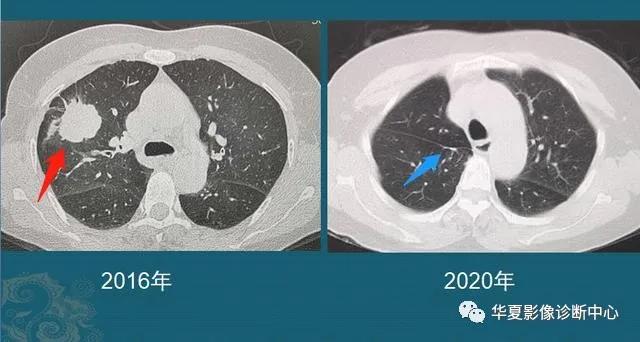

这是一位老年男性,有吸烟史,也是在两年多的时间内,肺结节从不足3mm长到1cm以上,后来病理确诊肺鳞癌。

中老年人定期胸部CT体检,可以及时发现这些生长较快的恶性肺结节,予以手术根治。